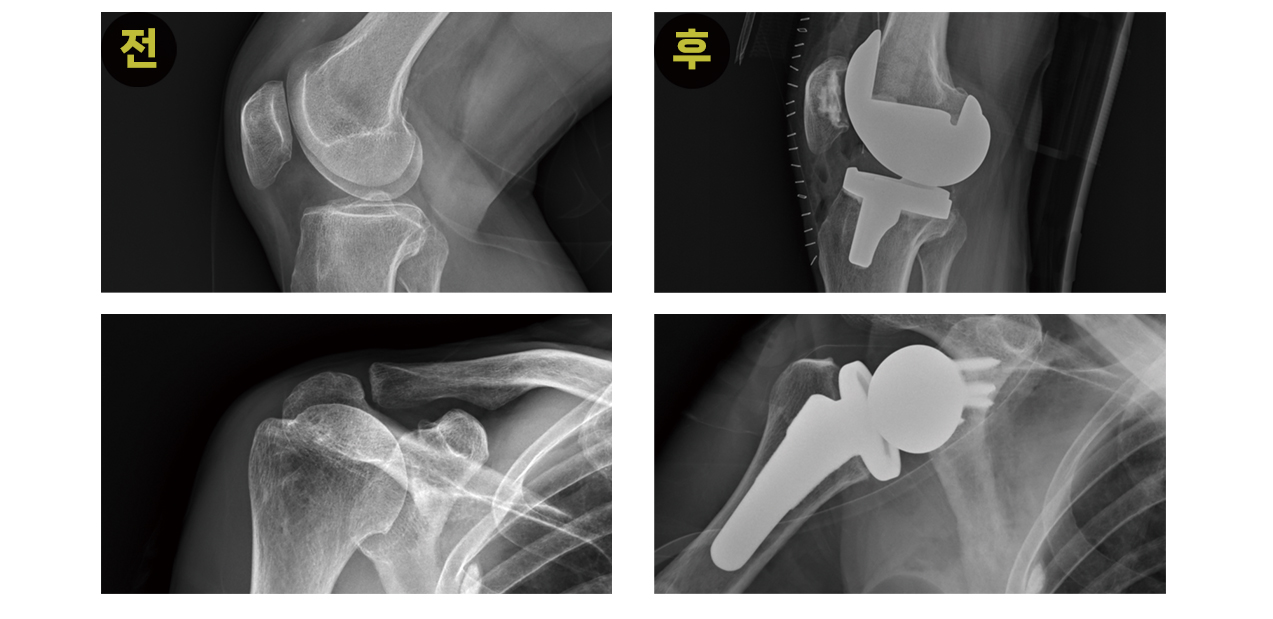

인공관절 치환술

실제 수술 진행사례

- 제 기능을 더 이상 하지 못하는 기존 관절 구조물을 제거하고 이를 인공적인 보형물로 교체하는 수술

- 최소침습으로 인공관절치환술을 진행할 수 있게 됨

- 관절의 손상 정도에 따라 일부 또는 전체를 교체하게 되므로 사전에 꼼꼼한 검사가 필요